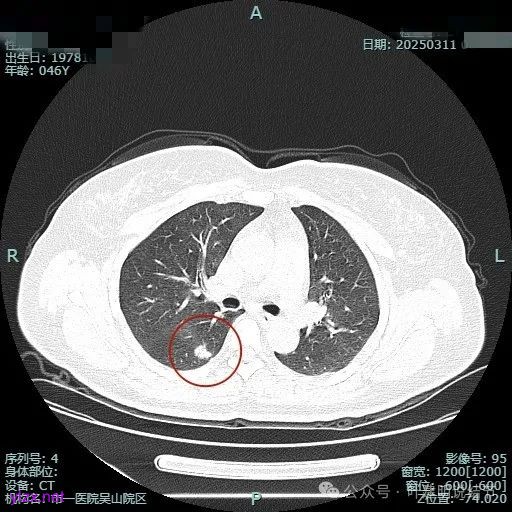

时间很快到了2025年3月,结友又来我门诊复查,我还以为她在别处开了刀了呢,结果并没有,说是与家人商量后决定吃中药三个月看看能不能好。我们来看看再复查的情况,中药有没有起作用:

总体感觉三处病灶边缘的淡磨玻璃成分好转不太明显了,实性成分较前略显致密点,大小与形态是说不上显著变化的。所以有几点可以肯定:1、消炎没有效;2、中药没有用;3、考虑多原发肺癌,且为浸润性腺癌可能性大些,得手术!

现病史:患者1年前于当地医院体检,行胸部CT提示肺部结节,平时无明显症状,无畏寒、寒战,无咳嗽、咳痰,无胸闷、胸痛,无恶心呕吐,无腹痛腹泻,无头晕头痛骨痛等不适,未予治疗。后定期复查,2025/3/11在杭州市肿瘤医院复查胸部(含纵隔)CT平扫+高分辨靶扫描:两肺纹理增粗,右肺下叶背段(SE4,IM95)可见实性结节,大小约14mm×10mm,可见分叶、胸膜凹陷征象。右肺中叶内侧段(SE4,IM137)可见实性结节,大小约6mm×5mm,可见胸膜凹陷征象。两肺内可见多发微小结节影,较大者位于右肺下叶内基底段(SE4,IM132)可见磨玻璃结节,大小约5mm×4mm。心影大小、形态正常;主动脉局部钙化。患者无畏寒、寒战,无咳嗽、咳痰,无胸闷、胸痛,无恶心呕吐,无腹痛腹泻,无头晕头痛骨痛等不适。为求进一步诊治来我院门诊就诊,拟“肺部阴影”收入我科。 患者起病以来,神志清,精神可,胃纳可,睡眠安,二便正常,体重近期无明显变化。 既往有“高血压”病史一年余,口服“苯磺酸氨氯地平片1#QD+奥美沙坦酯片1#QD治疗”控制血压,血压控制可。有“2型糖尿病”半年余,目前口服“达格列净片5mg1次/日”控制血糖。发现“肾病综合症”半年,目前无药物治疗。发现“右侧颈动脉及右锁骨下动脉斑块”半年,目前无药物治疗。有“高尿酸血症”病史,目前无药物治疗。